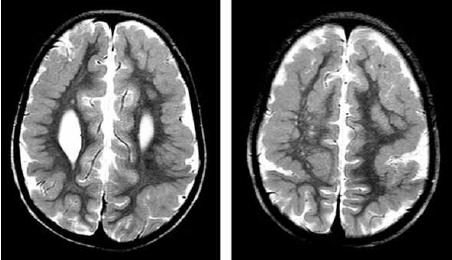

Paciente de 2 anos apresenta nistagmo e perda visual há 3 meses. Realizou o exame de imagem a seguir.

Enunciado 4100246-1

Qual é o provável diagnóstico?